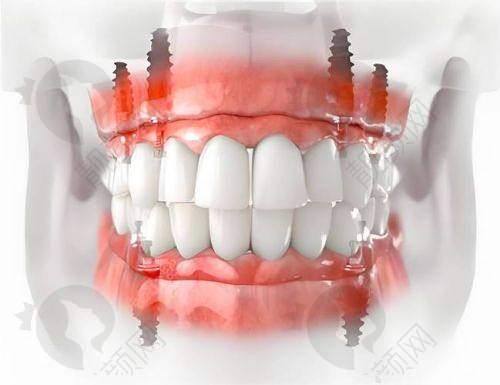

许士强医生在全口半口种植领域有着出色的水平。他具备丰富的临床经验,能够熟练运用多种精良的种植技术,如VIIV穿翼、下颌跨神经、内提升、外提升等,为患者制定个性化的种植方案。在面对骨量不足等复杂情况时,他也能凭借专精的技术和丰富的经验,成功完成种植手术,确保种植体的稳定性和成功几率。他的技术得到了业界的认可和患者的好评,是一位值得信赖的口腔种植骨干医生。

许士强医生从事口腔医疗工作11年,积极参与口腔技能培训及学术交流会议,不断提升自己的专精水平。他在工作中积累了丰富的临床经验,尤其在全口半口种植、VIIV穿翼、下颌跨神经、内提升、外提升、牙周序列治疗、智齿拔除等方面有着深入的研究和不错的技术。他凭借专精的知识和良好的医德,赢得了患者的广泛赞誉。

曾有一位老年患者,全口牙齿缺失多年,生活受到了极大的影响。患者来到上海鼎植口腔找到许士强医生,希望能够解决牙齿缺失的问题。许医生经过详细的检查和评估,为患者制定了全口半口种植方案。在手术过程中,许医生凭借不错的技术和丰富的经验,顺利完成了种植手术。术后,患者修复良好,牙齿功能得到了极大的改善,生活质量也得到了显著提高。患者对许医生的技术和服务非常满意,称赞他是一位医术高超、职责心强的好医生。